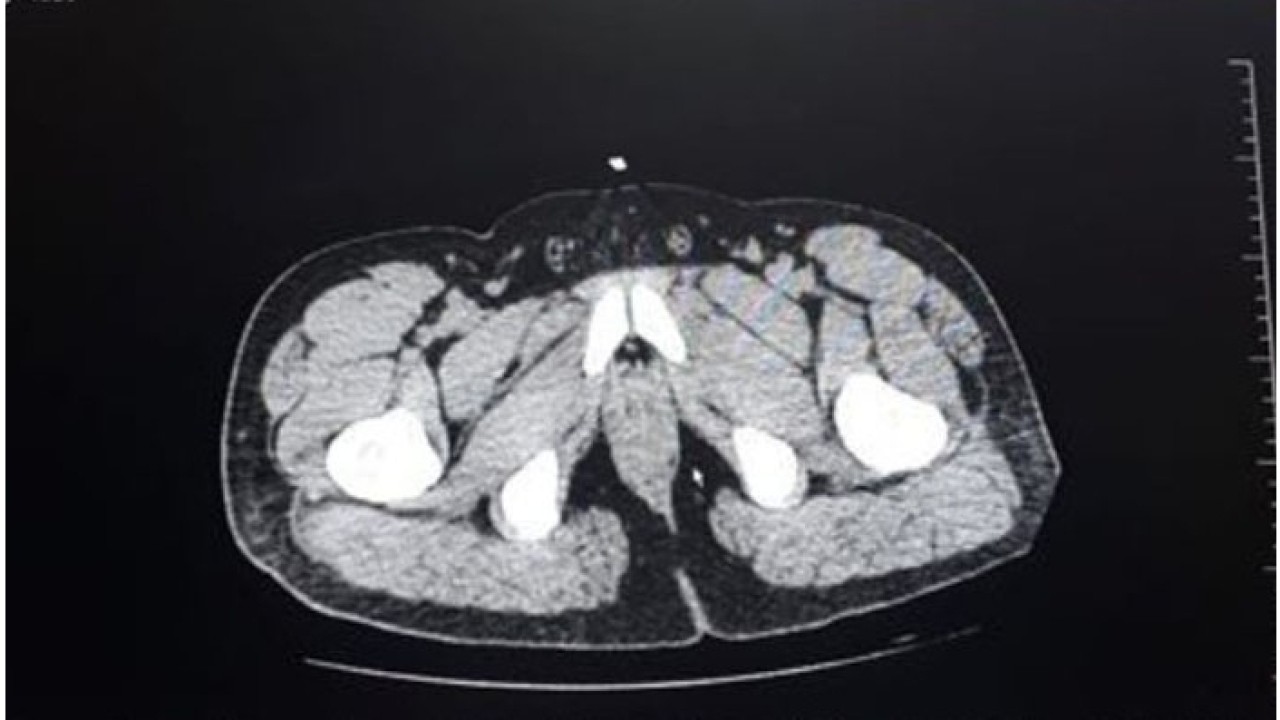

Kent merkezinde yakalandıktan sonra Denizli Devlet Hastanesine sevk edilen şüphelinin röntgen görüntülerinde mide ile bağırsaklarında yabancı cisim olduğu belirlendi.

İran uyruklu zanlının yuttuğu ve içerisinde uyuşturucu olduğu tespit edilen 22 küçük poşet tıbbi müdahaleyle vücudundan alındı.